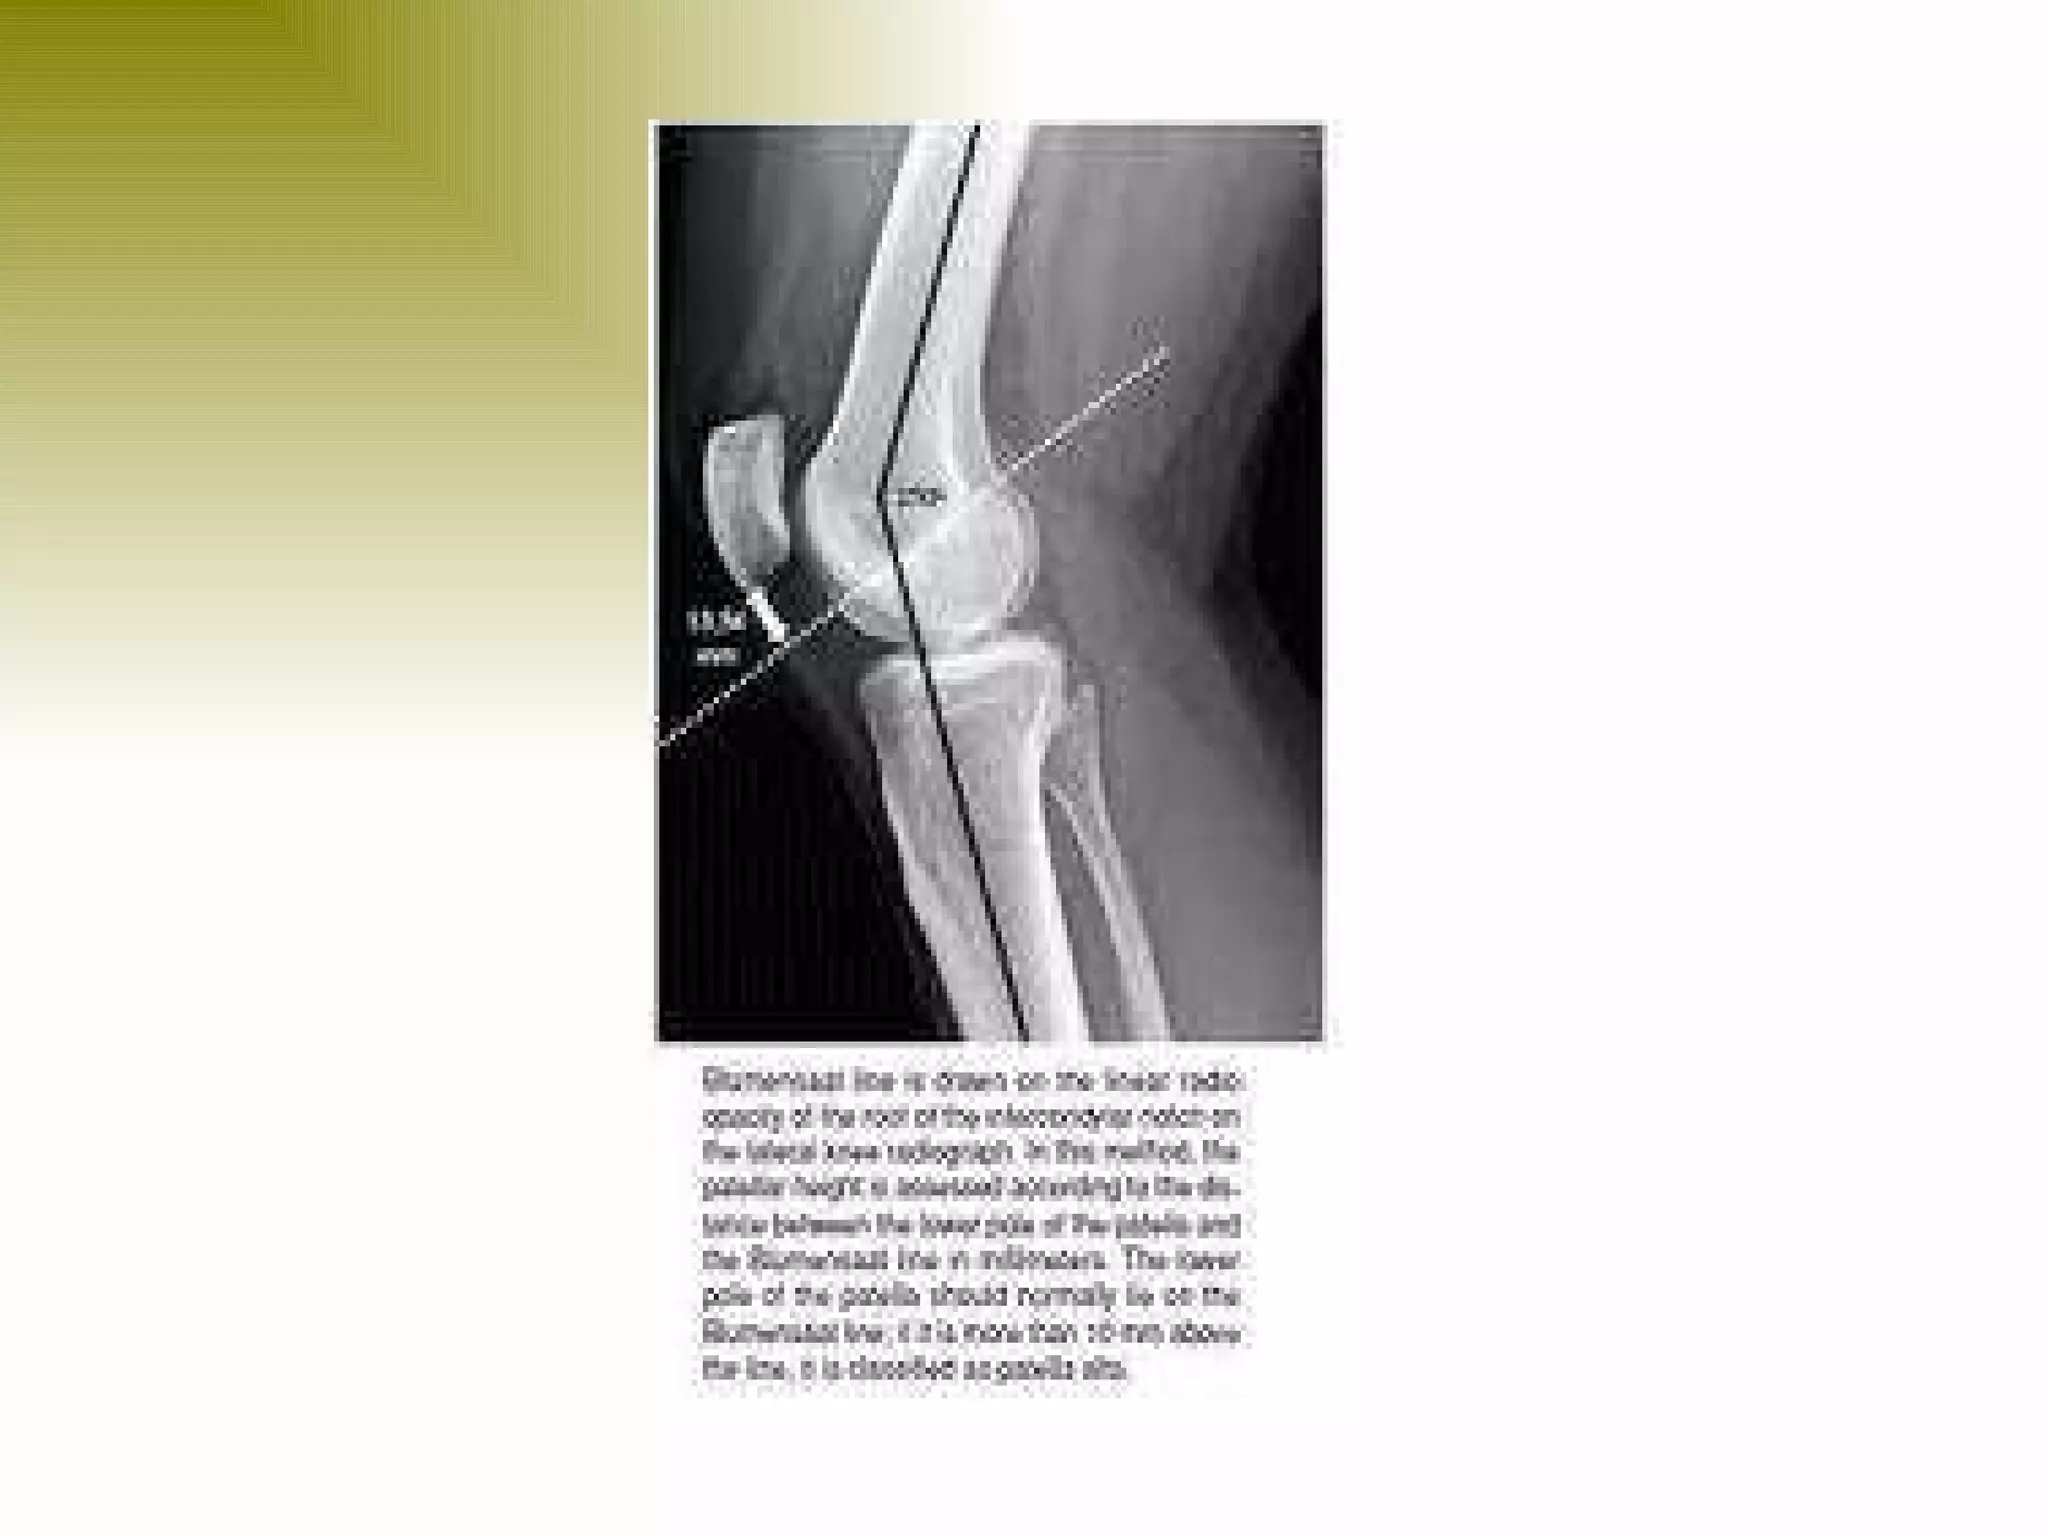

There are three types of patella dislocation: acute, recurrent, and habitual. Acute dislocation occurs suddenly due to quadriceps contraction with the knee flexed and results in the patella dislocating laterally, causing pain, swelling, and inability to straighten the knee. Recurrent dislocations are caused by ligament laxity or anatomical abnormalities and damage bones with repeated dislocations. Habitual dislocations occur every time the knee is flexed and present in early childhood.